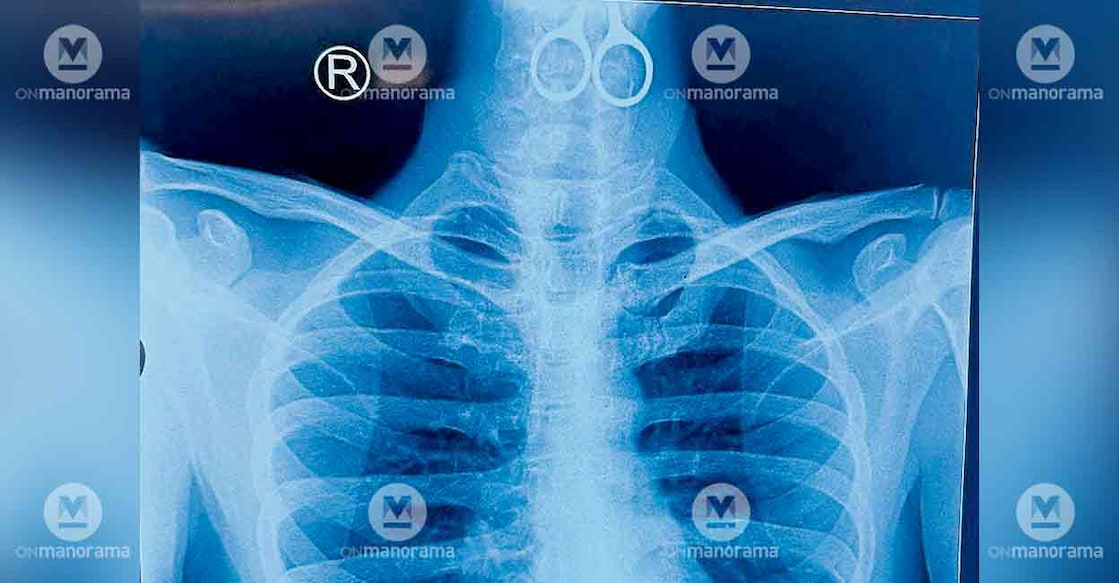

The patient, a young man, was admitted to the hospital's emergency department on Monday evening after he refused to take food. An X-ray examination revealed that a 15-cm-long pair of scissors was lodged in his oesophagus, following which he was immediately referred to the ENT department.

The 15-centimetre scissors successfully removed during surgery. Photo: Manorama